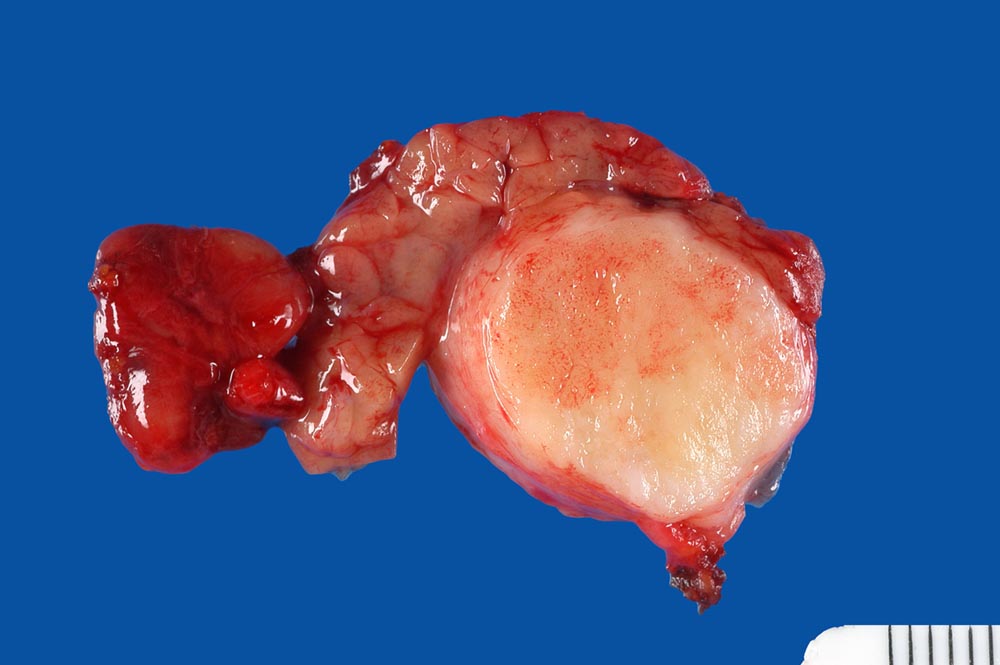

PathoPic ID 9536 - Pleomorphes Adenom der Glandula submandibularis

Pleomorphes Adenom der Glandula submandibularis

benigner Tumor

Glandula submandibularis

Kopf & Hals, Sinnesorgane

Innerhalb des makroskopisch unauffälligen Speicheldrüsengewebes findet sich ein bekapselter solider weissglänzender Tumor von 2cm Durchmesser.

Pleomorphes Adenom

Verdacht auf Karzinom der Glandula submandibularis

Makroskopie

16

männlich